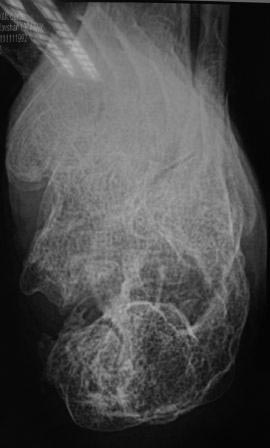

Постравматическая деформация пяточной кости

Уважаемые коллеги. Вчера госпитализирован пациент 1970г.р. , в ноябре 2014г, получил о/перелом пяточной кости. в другой клинике произведена КДО аппаратом Илизарова,

после трех месяцев аппарат сняли? , и больной начал наступать и ходить?- все это со слов б-ного(р-снимков нет.), Жалобы боли при ходьбе к-рая в динамике усиливается, об-но: деформация пяточной кости, движение в г/стоп.суставе почти в польном обьеме, по мед.поверхности пятки рубец плотно спаянный с костью.

Предварительный план: корригируюшая остеотомия пяточной кости, для создания свода стопы.( сможем ли опустить бугра пяточной кости из-за натяжения ахиллово сухожилия), и подтаранный артродез.